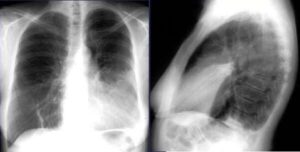

Сегментарная пневмония у взрослых — это вариант заболевания, при котором воспалительная реакция поражает только один сегмент легкого. Наиболее тяжелым проявлением является многосегментная пневмония (МКБ-10 — от J12 до J18 в зависимости от этиологических особенностей), когда процесс развивается одновременно в нескольких сегментах одного или обоих легких. Площадь поражения может быть довольно большой, что приводит к тяжелому …

Легкое — это парный орган с 3 долями справа и 2 слева. Каждая доля имеет определенное количество сегментов (в правом и левом легких их по 10). В верхней части левого легкого расположены язычные сегменты (верхний и нижний). Лингвальная пневмония — это подвид левосторонней высокодолевой пневмонии, то есть, в отличие от нижнедолевой пневмонии, поражаются тростниковые сегменты …